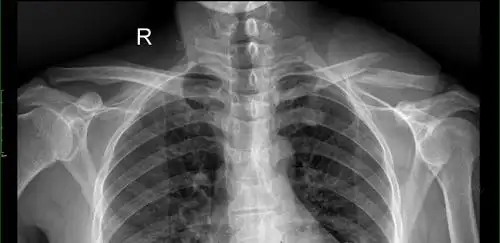

儿童锁骨骨折手术治疗(大于12岁)

右锁骨中段骨折

锁骨骨折x线片,正位片.

患者:普某,男,28岁,骑电动车摔伤导致左锁骨骨折,患者在当地人民医院